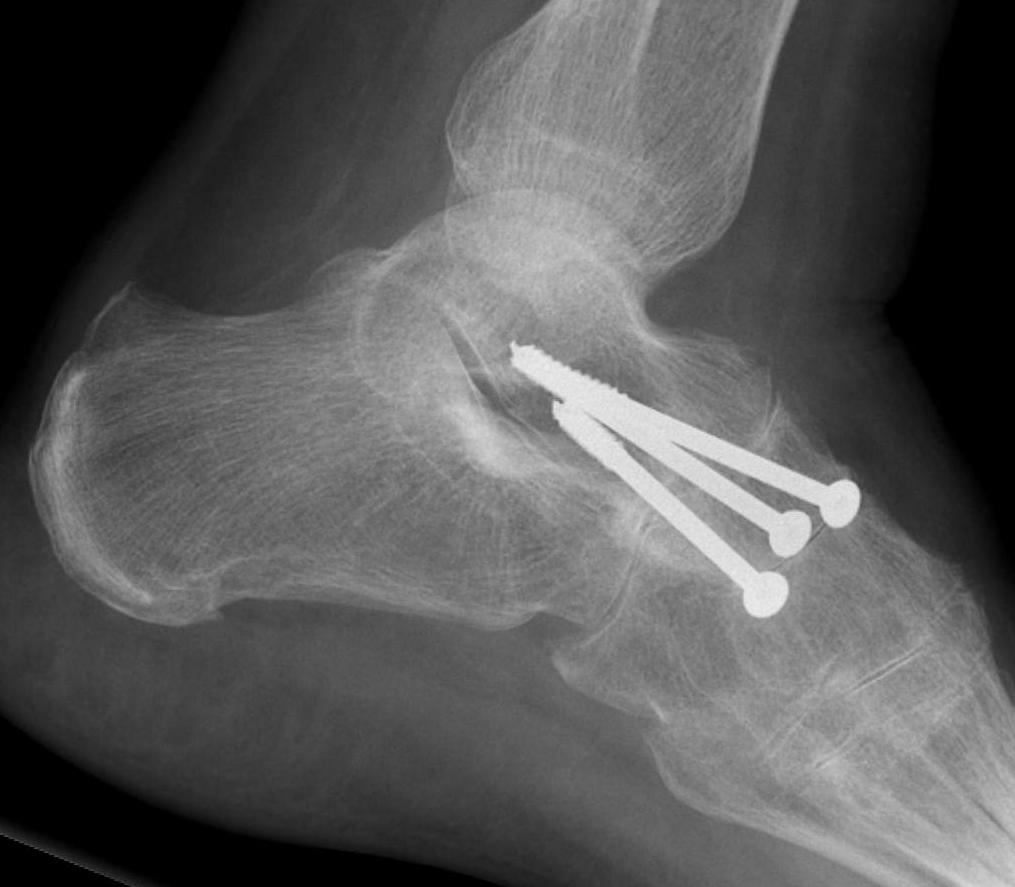

- isolated ankle arthrodesis in 20 RA patients

- 90% union rate